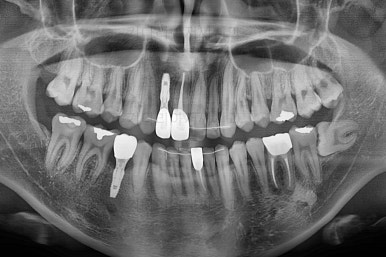

임플란트 완료시 모습인데요.

임플란트 식립부터 완료까지 시간이 걸리다보니 최종 종료까지는 총 19개월이 걸렸습니다.

교합도 잘 맞고 임플란트도 잘 완성되었네요.

매복치아도 손상 없이 잘 배열이 되었고, 교합도 좋게 마무리 되었습니다.